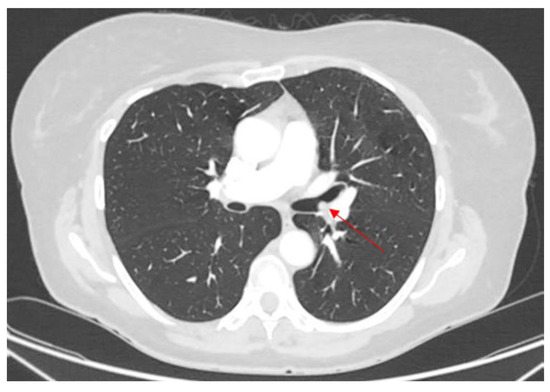

4.1. Case 1